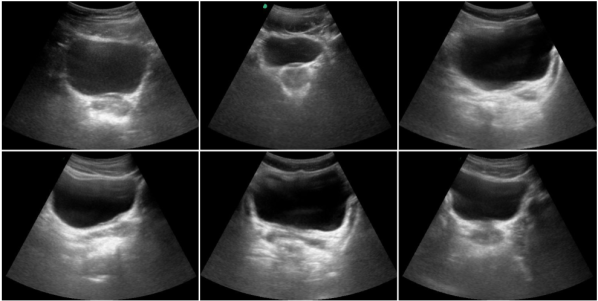

Refer to caption

Figure 1. Ultrasound images dataset of male pelvic view. The urinary bladder in pelvic view shows large variability in shape and size along with blurred boundaries, thereby making the task of segmenting it quite challenging.

There exist several challenges to automatic US image segmentation. Unlike MRI or CT, US images exhibit spurious effects due to variations in anatomical structures, the existence of blurred image boundaries, shadowing artifacts, and artifacts caused by patient movement or handheld movement of the probe (Noble, 2016). Some of these effects can be seen in Fig. 1, where UB is appearing in varying shapes and scales with indistinct boundaries, making the segmentation problem quite complex. In addition, manual segmentation by the sonographers causes inter- and intra-observer variability, thus restricting the reliability of UB diagnostics.